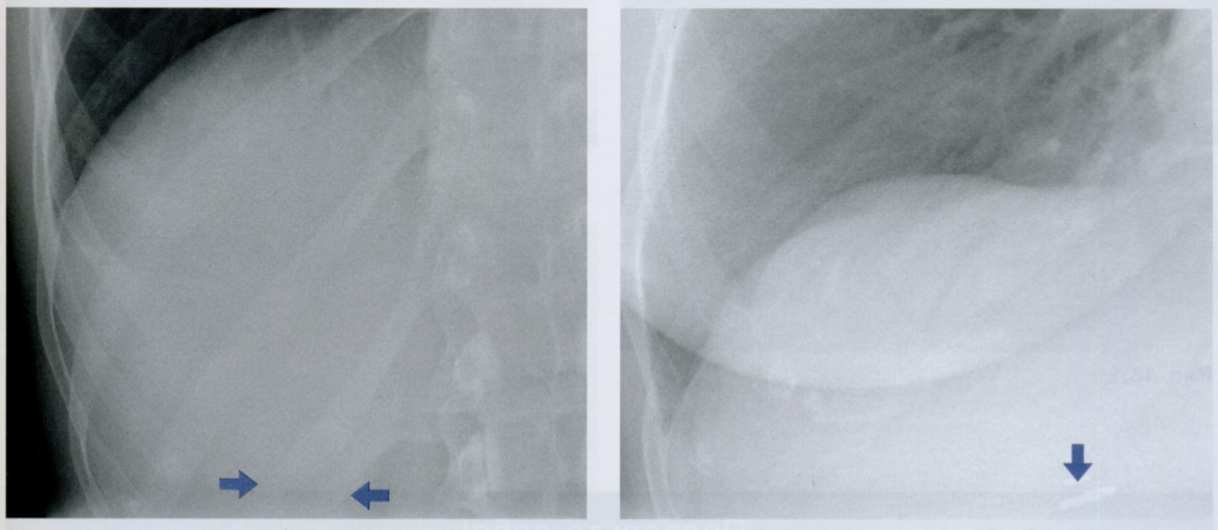

Оцените ассиметричность мягких тканей на снимке.

Обратите внимание на тень молочной железы (стрелочки), оцените симметричность теней слева и справа.

Ассиметрия прозрачности может наблюдаться после мастэктомий, радикального иссечения шейных лимфатических узлов, посттравматической гематомы грудной стенки, гепертрофии/атрофии мышц.

Пациентка после левосторонней мастэктомии с просветлением в нижних отделах с соотвествующей стороны (звездочка) в связи с отсутствием молочной железы (стрелочки).

Если есть сомнения, можно внимательнее рассмотреть подмышечную область на предмет возможного наличия металических клипс после иссечения ЛУ подмышечной впадины (фото ниже).

Ключевой момент - не ошибиться, принимая уменьшение прозрачности с одной стороны за выпот или внутрилегочное образование.